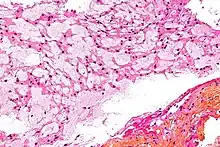

Microscópicamente, recuerda al tejido notocordal normal en sus distintos estadios de desarrollo. Crece en cordones celulares y lóbulos de células separados por una cantidad variable de tejido mucoide intercelular. Algunas de las células neoplásicas (conocidas como fisalíferas) son extremadamente grandes, con citoplasmas vacuolados y núcleos vesiculares prominentes. Algunas de las vacuolas citoplásmicas contienen glucógeno. Otras células tumorales son pequeñas, con núcleos inaparentes y sin nucléolos visibles. Generalmente hay pocas mitosis, o estas ausentes. Puede haber áreas de cartílago o hueso. Hay tres variantes histopatológicas del cordoma: clásica o convencional (la descrita), condroide y desdiferenciada.[7]